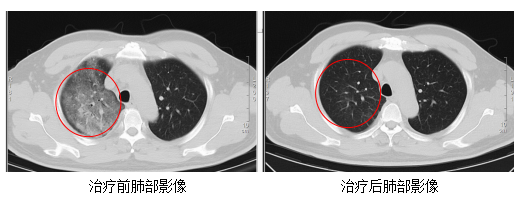

在感染科醫護團隊的精心治療與細緻護理下,顧先生的發熱、咳嗽、胸悶等症狀逐漸緩解。複查的CT結果顯示,肺部炎症情況得到了明顯的改善。目前,顧先生已經順利康復出院!